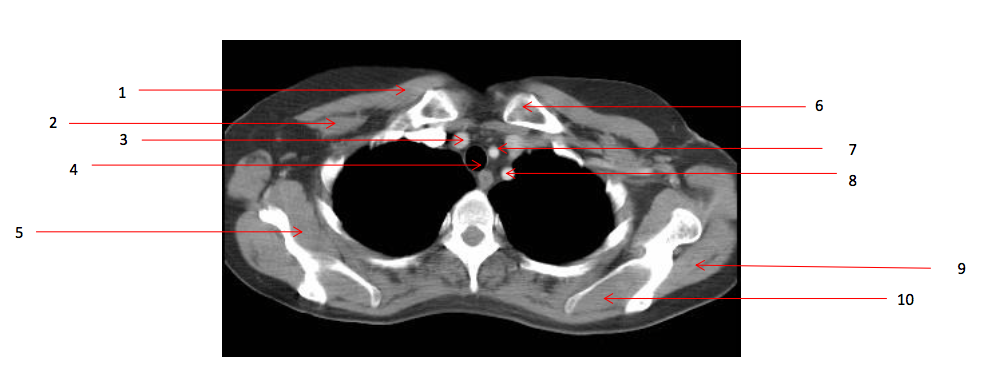

1

Rt pectoralis minor muscle

2

Lt clavicle

3

Lt supraspinatus muscle

4

5

Lt subclavian artery

6

Trachea

7

Lt common carotid artery

9

Rt subscapularis muscle

10

Rt erectae spinae muscle

11

Lt infraspinatus muscle

13

Lt scapula

15

Lt brachiocephalic vein

17

Sternum (manubrium)

18

Ascending aorta

19

20

Rt brachiocephalic vein

Q

Brachiocephalic artery